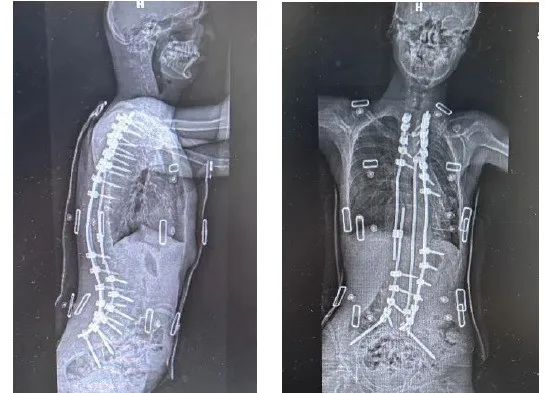

小寶術後的影像學結果。圖源/受訪者提供

2024年除夕前夕,小寶的住院治療階段結束,順利出院。此時,他的脊柱側彎角度從162度糾正至38度,後凸從109度糾正至36度;心肺功能明顯好轉,站姿、坐姿都肉眼可見得好了。父母驚喜地發現,孩子的身高從術前138釐米,增至162釐米。